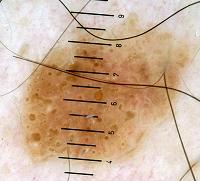

– Network-like pattern and fingerprinting : it doesn’t always resemble the pigmented network of benign melancytic lesions, which consist of grid-like {Menzies, 1996; Argenziano, 1998; Argenziano, 2000 ; Soyer, 2000; Kenet, 1993; Kreusch, 1991} {Stolz, 2002; Yadav, 1993} hyperpigmented lines surrounding hypopigmented zones. The lines of the network-like structures are much larger than those in the typical pigment network and may end abruptly at the periphery {Braun, 2002}. {Braun, 2002}The lines correspond to mild epidermal hyperplasia, hyperkeratosis and an increase of melanin in the keratinocytes {Schiffner, 2000}. The holes, which are much larger than in the melanocytic grid-like network, often correspond, as with fissures and comedo-like openings, to keratin-filled structures, not always to the tips of dermal papillae {Schiffner, 2000}.

– Moth-eaten borders {Schiffner, 2000} are truncated irregular borders seen in early SKs and solar lentigos.

– Sharp dermarcation {Braun, 2002} is present in nearly 90% of lesions in a study of 204 pigmented SKs .

– Some characteristics are more frequent than others. According to one study {Braun, 2002} of 203 pigmented SKs, the most frequently found lesions were milia-like cysts (135) and comedo-like openings (144 lesions), followed by hairpin vessels and fissures. 183 lesions were sharply demarcated. Nevertheless, the weakness of this study is that it aims pigmented SKs, not seborrheic keratosis as a whole. That means that the 94 network-like structures found are an overestimated figure.

According to our experience we evaluated the frequency of characteristics. The lesions were shown to us after being clinically diagnosed by clinicians as SK. The three most specific criteria for diagnosing SKs were sharp delineation, milia-like cysts and comedo-like openings. The presence of these three characteristics together is very specific. It diminishes in diagnostic power when one of these three features is absent.